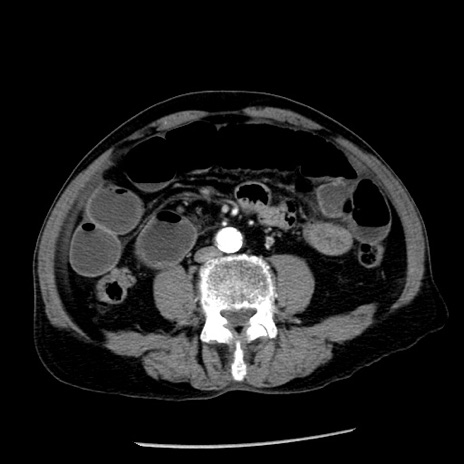

症例26(横断像)

【症例】80歳代男性

【主訴】嘔吐

【現病歴】昨晩2回嘔吐あり、今朝になっても嘔吐あり。来院。

【既往歴】胃潰瘍

【身体所見】意識清明、BT 37.6℃、BP 166/95mmHg、HR 100bpm、SpO2 97%、腹部:平坦・軟、腸蠕動音聴取良好、圧痛なし。

【データ】WBC 21900、CRP 1.46